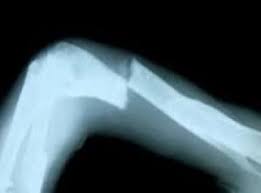

kol kırılması nasıl anlaşılır

kol kırılması nasıl anlaşılır.

kirik kemik nasil anlasilir sifa danismanlik